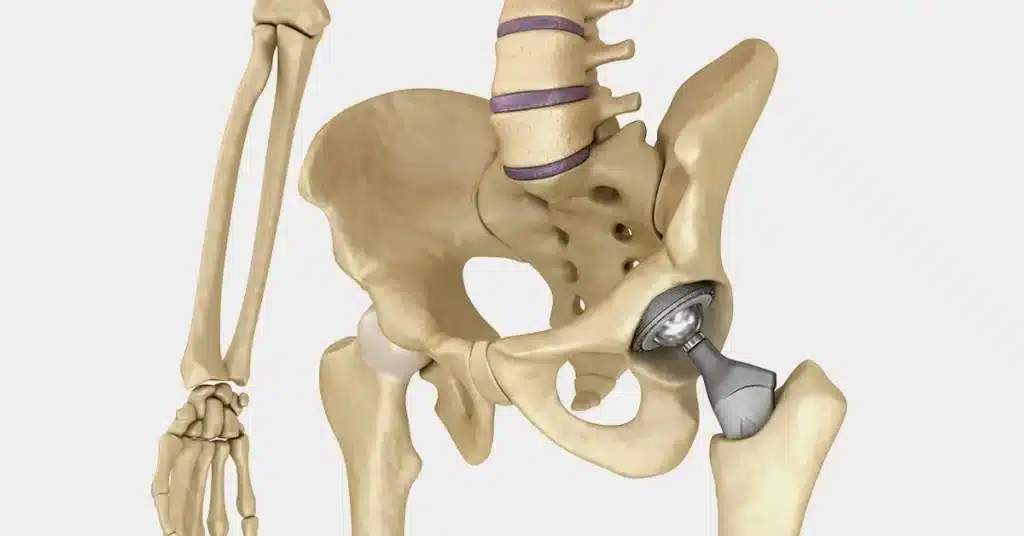

پروتز لگن یا همان پروتز مفصل لگن، یکی از رایجترین روشهای درمانی در حوزه ارتوپدی است که برای بهبود عملکرد مفصل ران و کاهش درد ناشی از آسیبدیدگیهای شدید یا آرتروز پیشرفته استفاده میشود. این روش که بهنام ارتوپلاستی مفصل ران و لگن نیز شناخته میشود، شامل جایگزینی مفصل طبیعی با یک پروتز مصنوعی است. […]

قیمت مفصل مصنوعی لگن

قیمت مفصل مصنوعی لگن بسته به برند، کشور سازنده و نوع پروتز متفاوت است. آگاهی از این موارد برای تصمیمگیری درست قبل از جراحی ضروری است. برای مشاوره با ما تماس بگیرید: 09106063586 همهچیز درباره قیمت مفصل مصنوعی لگن؛ از برند تا نوع پروتز ✔ ✅ قیمت انواع مفصل مصنوعی لگن بر اساس برند و […]